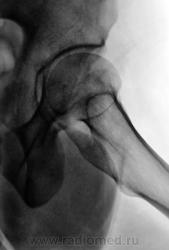

очаг в подвертельной области - вряд ли артроз...

Наряду с очагом в головке, видится мне ещё и перелом - линейное нарушение кортикального слоя. И ещё очаг в крыле подвздошной кости (но может и придираюсь). Я бы взял изначально на МРТ таза и тазобедренных суставов.